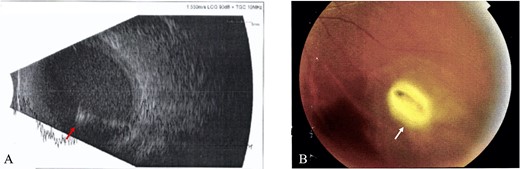

The most common IOFB material was metallic (iron) in six patients due to projectile hammering; two patients were injured by glass fragment (blast and MVA, respectively) and one patient by projectile stone particle. All patients underwent surgeries, and even though there were some difficulties during the extraction, all IOFBs were successfully removed. In Case 4, the IOFB fell twice on to the retina, causing retinal hemorrhage. Two retinal breaks were observed; one break was at inferior temporal; one iatrogenic break was at perimacular area, which occurred during IOFB removal and caused additional hemorrhage in the vitreous. Finally, it was successfully removed by scleral incision using IOFB forceps, shown as a metallic object with the size of 3 × 5.5 mm. The hemorrhage was controlled, laser barrage was applied and silicon oil 1000 c was injected as tamponade (Fig. 5). Six patients had better final VA, with mean final VA 1.1 ± 0.89 logMAR (ranged from LP to 20/20). Initial and final VA is presented in Fig. 6.

Difficulties during the IOFB extraction in Case 4; (A) A large size metallic iron IOFB was embedded in retina and a retinal break was discovered at inferior temporal, after applied laser barrage to secure the break, the IOFB was removed, (B) The IOFB fell twice on to the retina, but it was successfully removed by scleral incision using IOFB forceps, shown as a metallic object with the size of 3 × 5.5 mm, (C) Retinal hemorrhage after removal was showed and the hemorrhage was managed, (D) One iatrogenic break at perimacular area was found during the removal and caused additional hemorrhage in the vitreous; the hemorrhage was controlled, laser barrage was applied and silicon oil 1000 c was injected as tamponade.